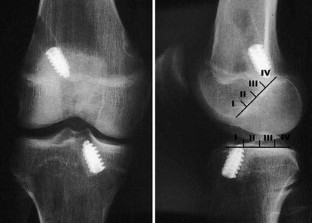

Patellar tendon graft has been the most frequently used material in anterior cruciate ligament (ACL) reconstruction, but the hamstring tendons have been increasingly used as well; however, which graft is to be preferred is not adequately supported by existing clinical studies. In this prospective randomized clinical trial, the study hypothesis was that the hamstring tendons are equally good graft material as the patellar tendon in ACL reconstruction. Ninety-nine patients with laxity due to a torn ACL underwent arthroscopically assisted reconstruction with graft randomization according to their birth year to either patellar tendon with metal interference screw fixation or double looped semitendinosus and gracilis tendons with fixation similar to the Endobutton technique using a titanium metal plate suspension proximally and screw-washer postdistally. Excluding preoperative Lysholm knee score, there were no significant differences between the two groups in the preoperative and operative data. A standard rehabilitation regimen was used for all the patients, including immediate postoperative mobilization without a knee brace, protected weight bearing for 2 weeks, and return to full activity at 6–12 months postoperatively. Forty patients in the patellar tendon group and 39 patients in the hamstring tendon group were available for clinical evaluation at median 5 years after surgery (ranges 3 years 11 months–6 years 7 months). The results revealed no statistically significant differences with respect to clinical and instrumented laxity testing, isokinetic muscle torque measurements, International Knee Documentation Committee ratings, Lysholm (knee score), Tegner (activity level) and Kujala patellofemoral knee scores. There was an enlargement of the drill tunnels, statistically more in the hamstring tendon group, but no increase from 2 to 5 years in either group. Narrowing of the joint spaces (IKDC measurement method) from 2 to 5 years postoperatively was seen in both the groups, however, without difference between the two groups.

Fig. 2